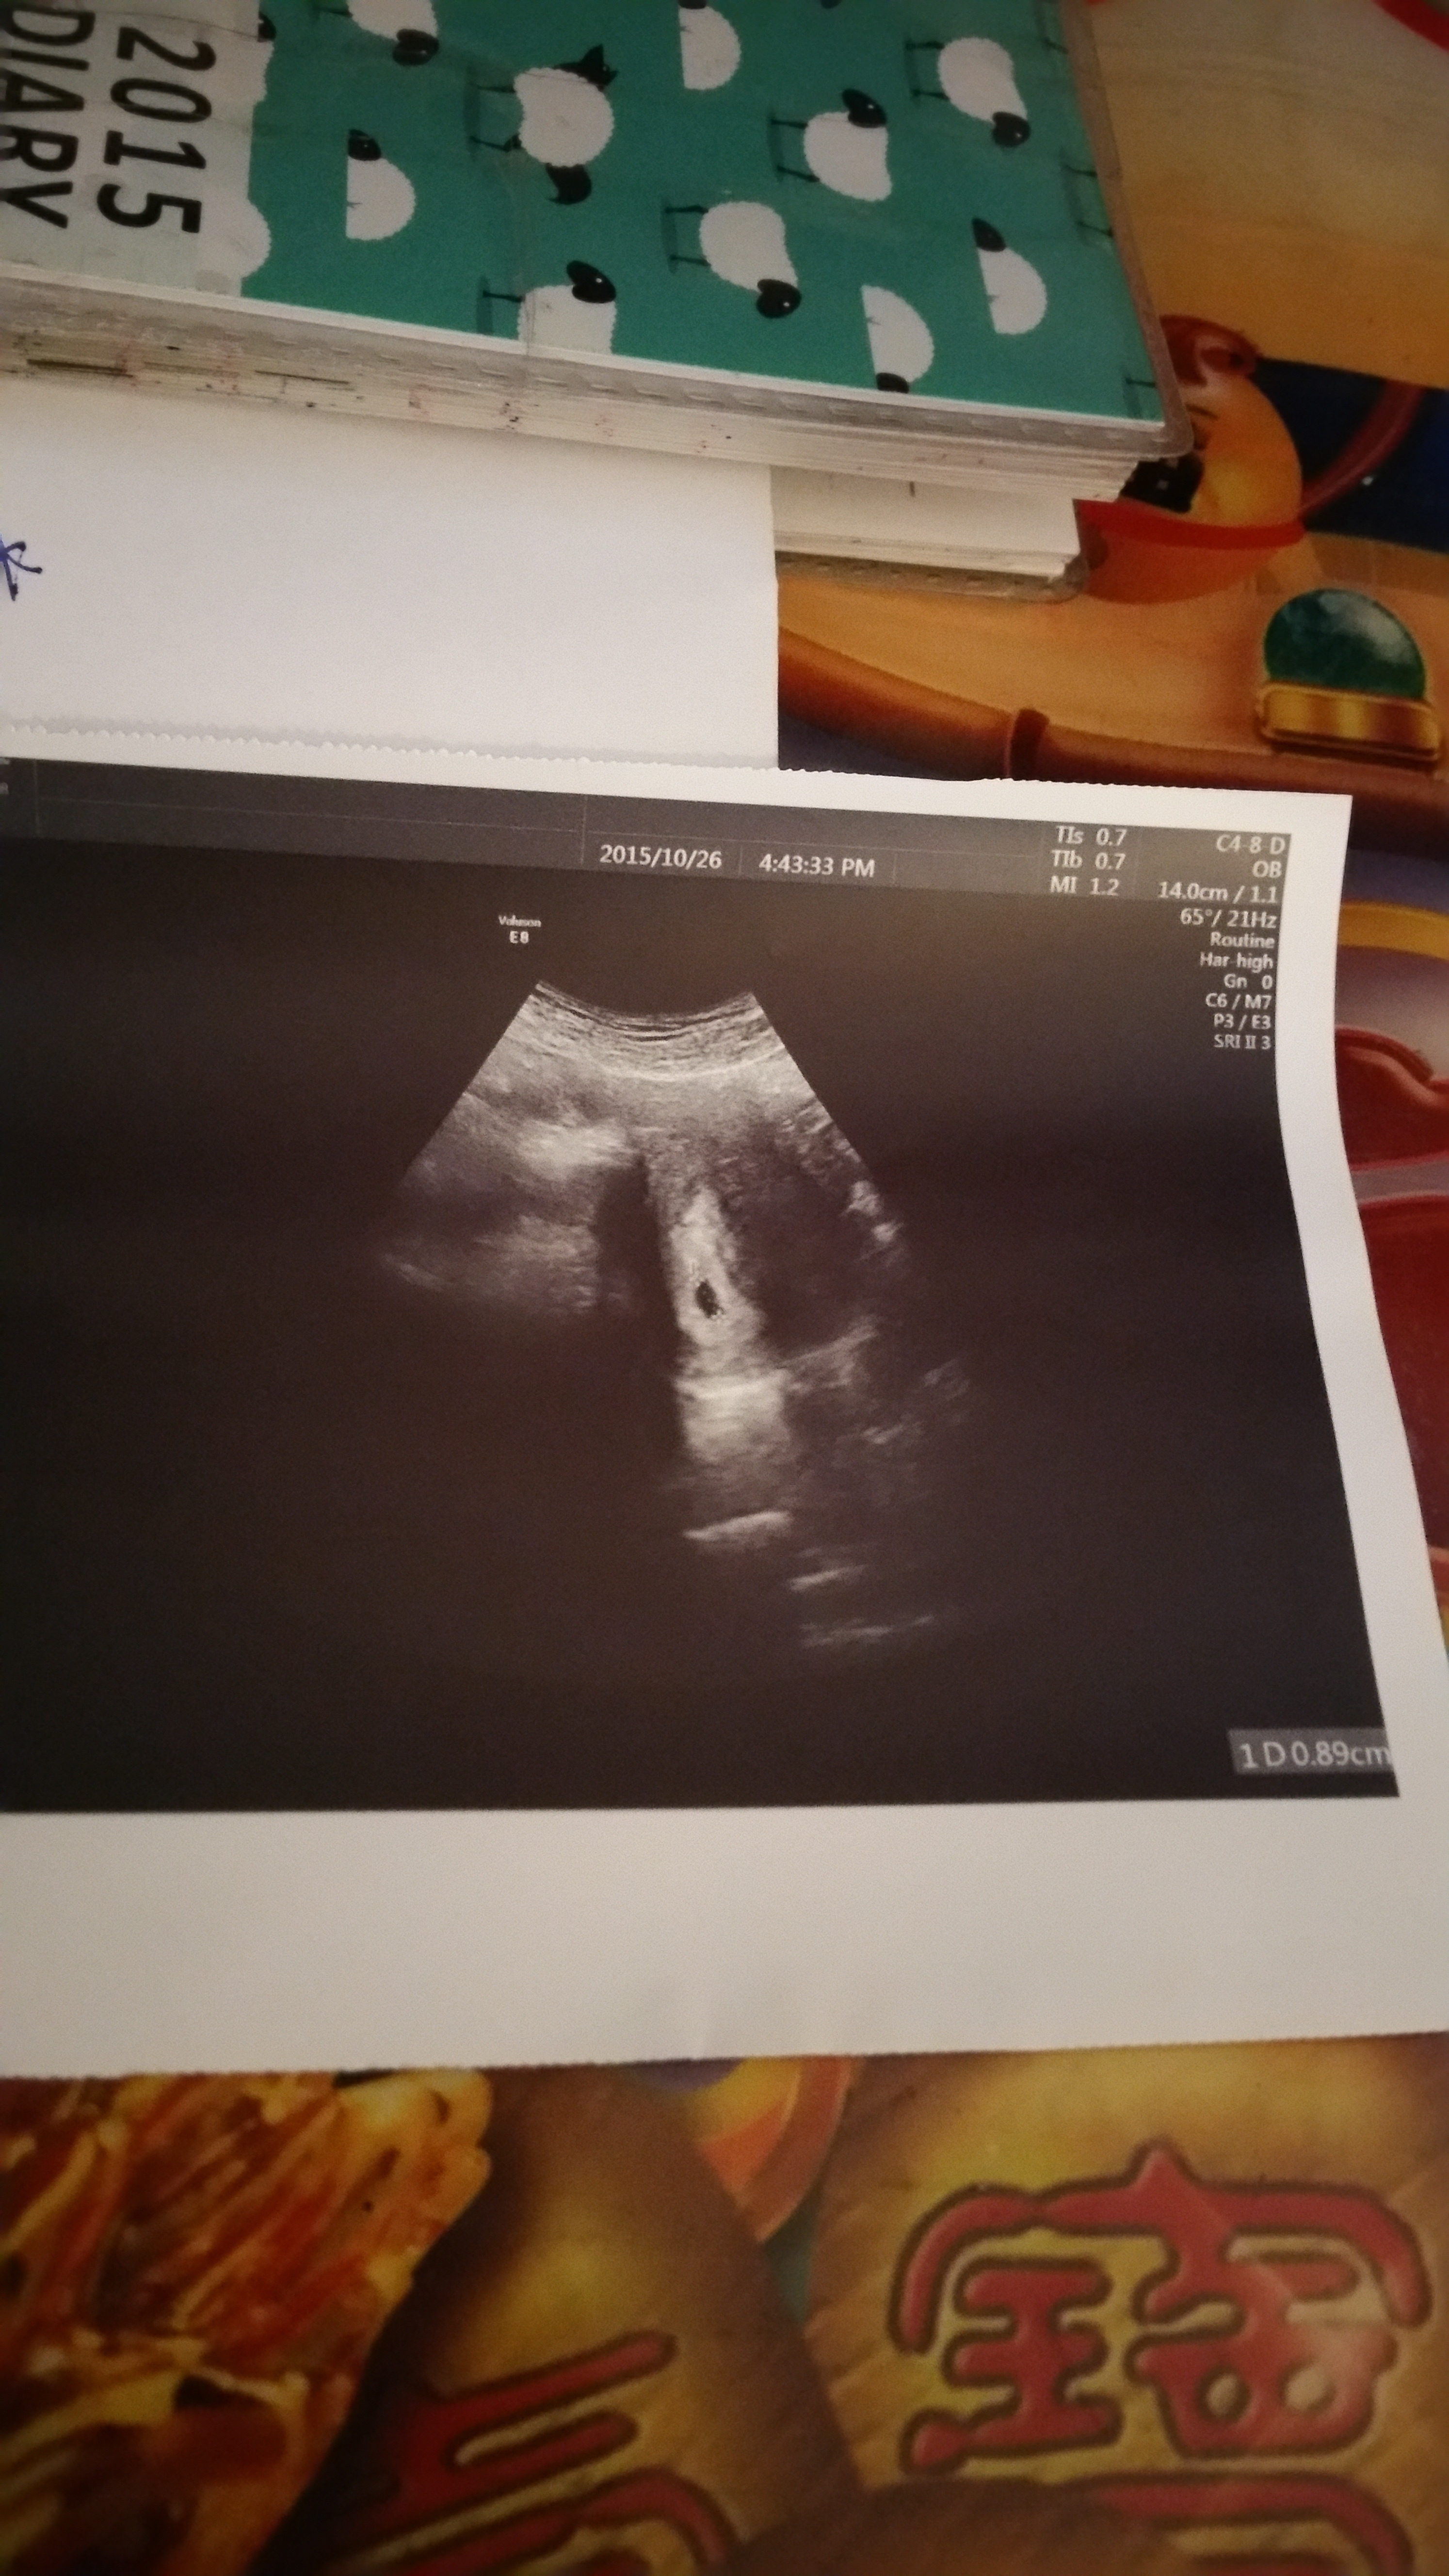

四週照腹超一下子就照的那麼清楚了!是寶寶在提醒我不要忘了他的存在嗎?

看版上很多水水說4週不是都照不太到嗎?

0.89公分,醫生說是正常大小。二個禮拜再回去照心跳。